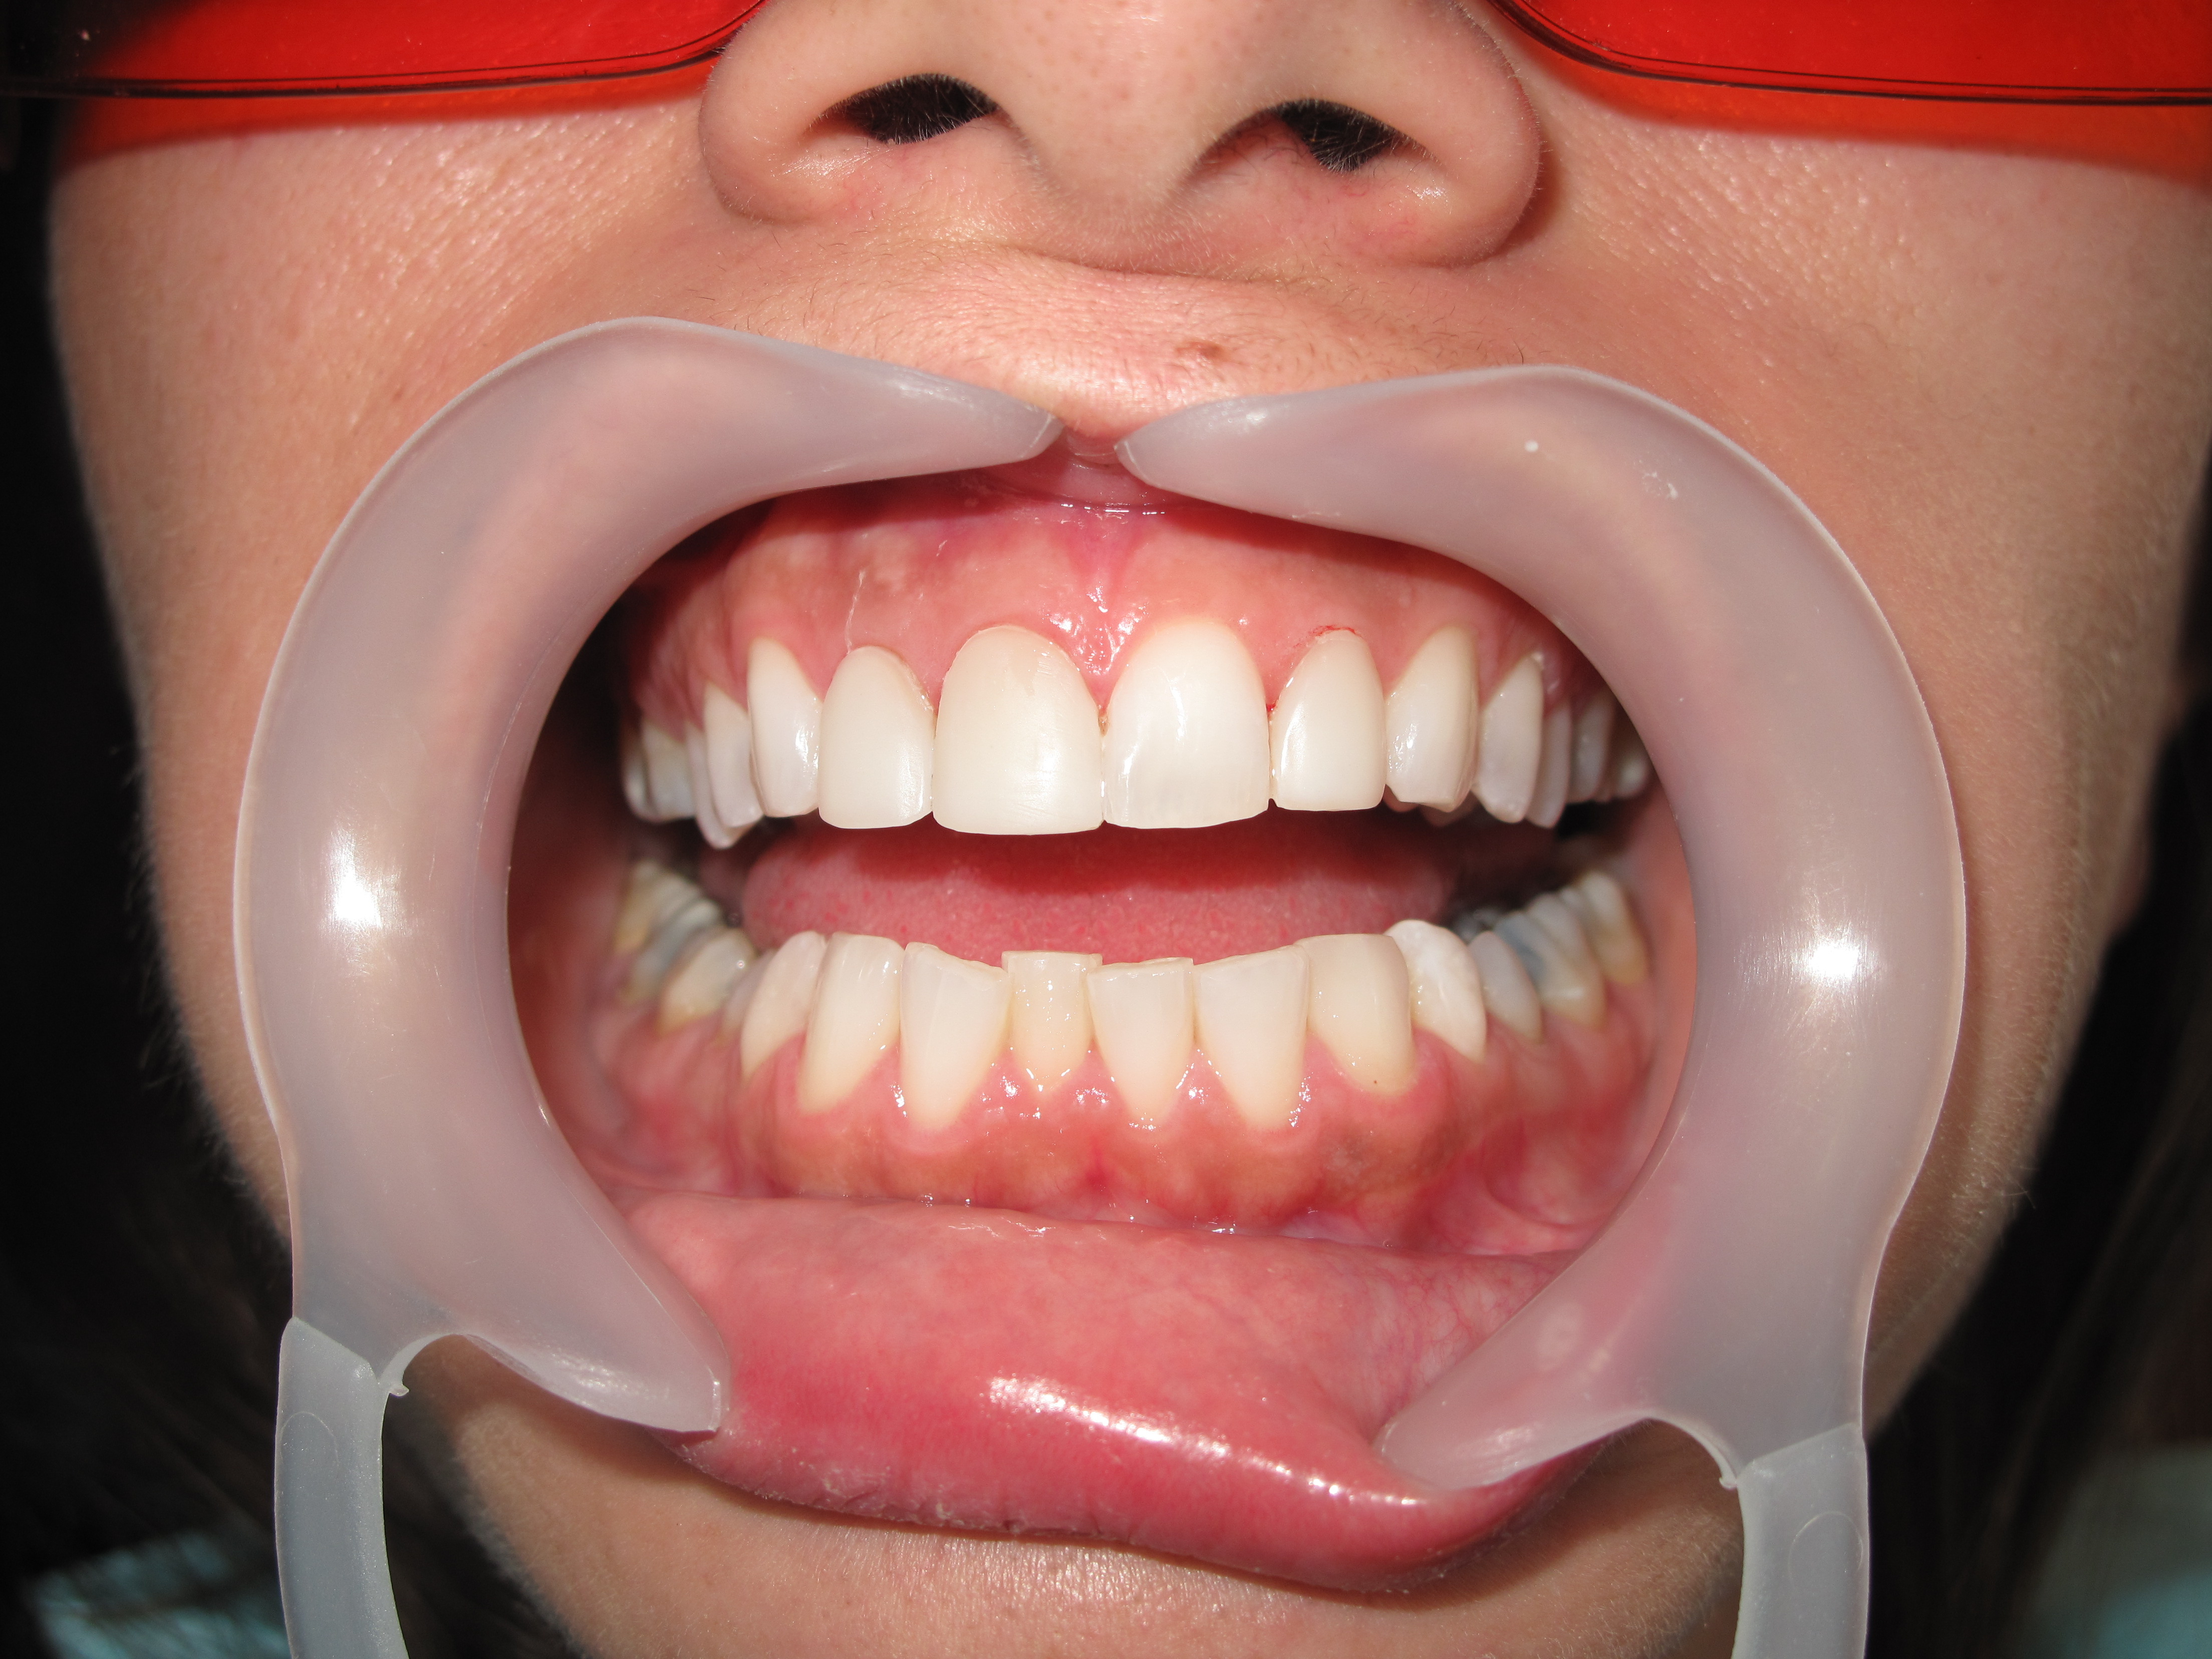

Best Dental implants dentist in Lebanon Beirut with Laser assisted technology Dr. Habib Zarifeh head of Clemenceau Medical center Oral surgery dental clinic affiliated with Johns Hopkins International.

Dental implants surgery should always be performed by Oral surgery or dental surgeon specialist, also called periodontist and oral surgeon to minimize the risks of this very accurate procedure.

Dental implants are most difficult in the esthetic zone especially when it needs Bone graft management.